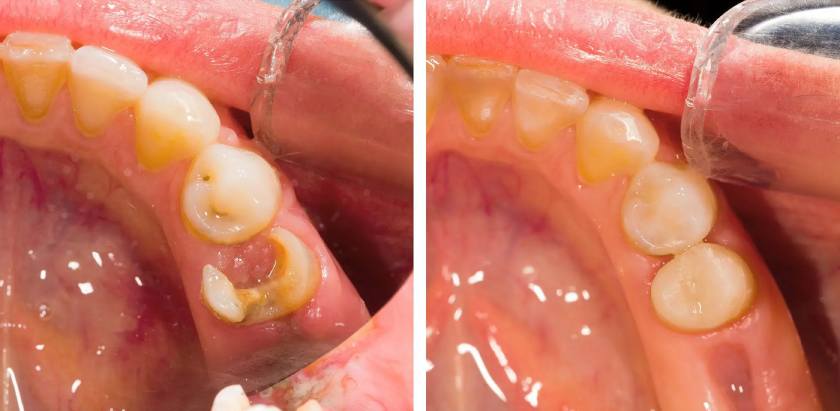

Trám răng thẩm mỹ là phương pháp phục hình nha khoa sử dụng vật liệu trám để khôi phục răng bị sâu, bị mẻ, vỡ… trở lại hình dạng ban đầu.

Công dụng của kỹ thuật trám răng là phục hồi chức năng ăn nhai và thẩm mỹ cho răng, nâng cao chất lượng cuộc sống và sự tự tin cho bệnh nhân. Bạn có thể tham khảo hình ảnh trám răng bên dưới để hình dung rõ hơn về giải pháp phục hình này.

Nếu răng bị sâu hay viêm tủy thì sẽ cần điều trị sâu răng và chữa tủy. Sau đó, Bác sĩ dùng mũi khoan chuyên dụng để tạo hình xoang trám phù hợp với vật liệu trám răng đã chọn.

Bước 4: Trám răng

Tiến hành cho vật liệu trám răng vào xoang trám. Vật liệu trám mới đầu ở dạng lỏng và sẽ dần đông cứng dưới tác động của ánh sáng Laser (thường mất khoảng 40 giây).